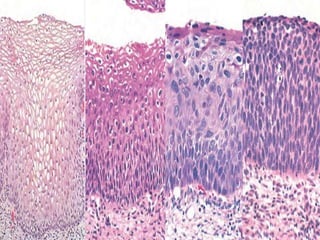

• #47 Spectrum of cervical intraepithelial neoplasia: normal squamous epithelium for comparison; LSIL (CIN I) with koilocytic atypia; HSIL (CIN II) with progressive atypia and expansion of the immature basal cells above the lower third of the epithelial thickness; HSIL (CIN III) with diffuse atypia, loss of maturation, and expansion of the immature basal cells to the epithelial surface.

• #48 The cytology of cervical intraepithelial neoplasia as seen on the Papanicolaou smear. Normal cytoplasmic staining in superficial cells (A and B) may be either red or blue. A, Normal exfoliated superficial squamous cells. B, Low-grade squamous intraepithelial lesion (LSIL)—koilocytes. C, High-grade squamous intraepithelial lesion (HSIL; CIN II). D, HSIL (CIN III). Note the reduction in cytoplasm and the increase in the nucleus-to-cytoplasm ratio, which occurs as the grade of the lesion increases. This reflects the progressive loss of cellular differentiation on the surface of the lesions from which these cells are exfoliated. (Courtesy Dr. Edmund S. Cibas, Brigham and Women’s Hospital, Boston, Mass.)